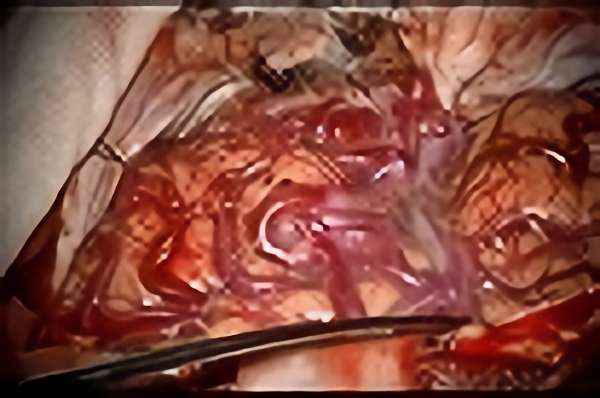

'19年5月

30代

富永/久貝

右中小脳脚 出血再発

SM 3(S1,E1,V1)

米国の病院

No.359 モニタリング

No.359 手術前

No.359 手術中

No.359 手術後

出血既往があり。2回の手術前血管内手術の後に、

Lateral transpeduncular approachにより再々出血予防を目的に

摘出手術を行う。完全摘出であることを確認した。

手術による合併症や後遺症なしで退院した。経過良好。